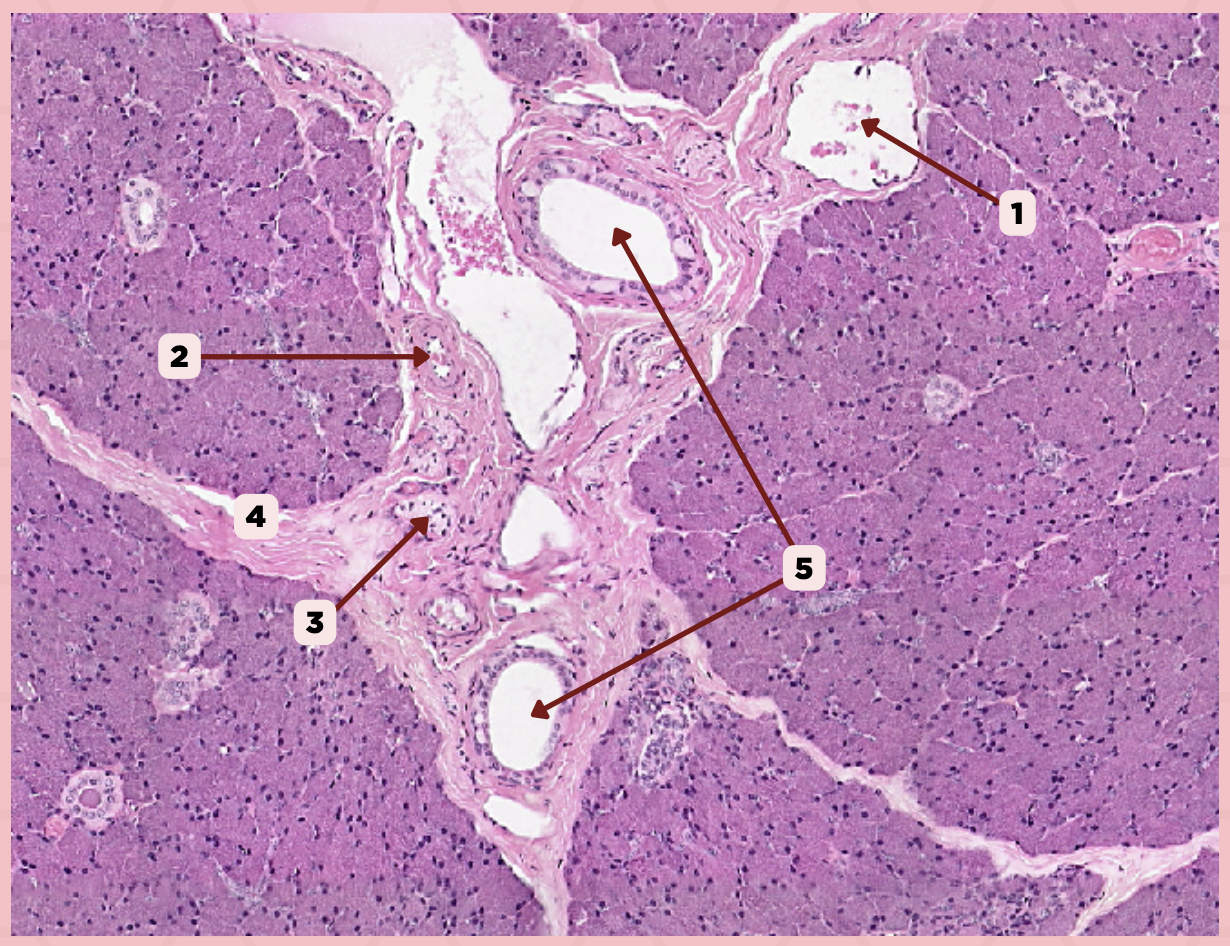

Parotid

Identify the specimen.

Capsule

Identify the structure labeled as 1.

Septa

Identify the structure labeled as 2.

Lobule

Identify the structure labeled as 3.

Lymph Node

Identify the structure labeled as 4.

Vein

Identify the structure labeled as 1.

Artery

Identify the structure labeled as 2.

Nerve

Identify the structure labeled as 3.

Interlobular Septa

Identify the structure labeled as 4.

Interlobular Duct

Identify the structure labeled as 5.